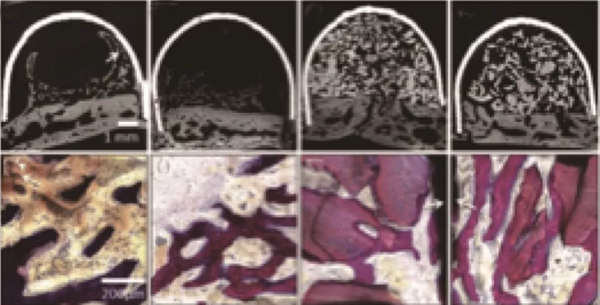

因為PRF中含有生長因子,而體外實驗也證明了這些生長因子具有一定的促進成骨效果。學者也將其應用到了促進成骨的動物實驗中,Knapen等在兔的顱骨中研究了PRF的促進成骨效果[5],結果在組織學和組織形態(tài)定量學的分析中(圖2、3)都沒能發(fā)現(xiàn)PRF有任何附加的影響。

Nejat在上頜竇外提升術中研究了PRF促進成骨的效果[6],在實驗中對照單獨使用Bio-oss和Bio-oss聯(lián)合PRF在上頜竇提升術中的應用,在6個月的愈合期之后,對新生骨進行組織學和組織形態(tài)定量分析(圖4),發(fā)現(xiàn)兩組沒有差異。這就說明了PRF的使用并不能帶來更多更好的成骨效果。